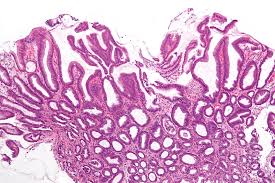

Changes in the gastroesophageal junction and distal esophagus secondary to reflux of gastric or duodenal contents into the esophagus; Esophagitis caused by herpes simplex virus (hsv) is frequently documented during periods of immunosuppression in patients infected with human immunodeficiency virus (hiv). The esophagus is a muscular tube that carries food and drink from your mouth to your stomach. Acute esophagitis is manifested here by increased neutrophils in the submucosa as well as neutrophils infiltrating into the squamous mucosa at the right. We reviewed 16 cases of hsv esophagitis diagnosed from january 1982 to march 2016. Hsv isolation from esophageal tissue (culture or polymerase chain reaction). The diagnosis of herpes simplex virus (hsv) esophagitis is made at endoscopy. Endoscopic examination was performed du … Elongated papillae >2/3 of the thickness of the mucosa The diagnosis of hsv and cmv esophagitis, and to develop a predictive model for differentiating cmv esophagitis from hsv esophagitis. The patients usually present with odynophagia, chest pain, malaise, and fever. Clinical characteristics and endoscopic features were retrospectively reviewed and categorized. Herpes simplex virus (hsv) is a common cause of infectious esophagitis.

Esophagitis caused by herpes simplex virus (hsv) is frequently documented during periods of immunosuppression in patients infected with human immunodeficiency virus (hiv). Lymphocytic esophagitis is characterized by high numbers of intraepithelial lymphocytes (iels) gathered mainly around peripapillary fields and by none (n = 12) to occasional (n = 8) cd15+ intraepithelial granulocytes. The histology of herpes infections is very distinctive. The acute inflammation can be caused by infections, ingestion of irritative chemicals, drugs such as nsaids, chemotherapy, and radiation. His immunological work up showed normal level of immunoglobulins and his white blood cells subpopulations were normal. We reviewed 16 cases of hsv esophagitis diagnosed from january 1982 to march 2016. The low power pattern of a typical lesion. Hsv esophagitis is usually identified in patients with aids or other significant immunosuppressive conditions, although cases in healthy adults also occur.

Hsv esophagitis is usually identified in patients with aids or other significant immunosuppressive conditions, although cases in healthy adults also occur. He had no history of recurrent infections or history of sick contacts. This condition can also occur as a primary infection in individuals taking immunosuppressive drugs and it is therefore considered as an opportunistic disease [ 1 Forms of esophagitis have been recognized for millennia; His immunological work up showed normal level of immunoglobulins and his white blood cells subpopulations were normal. His hsv serology was positive. We reviewed 16 cases of hsv esophagitis diagnosed from january 1982 to march 2016. Acute esophagitis is manifested here by increased neutrophils in the submucosa as well as neutrophils infiltrating into the squamous mucosa at the right. We reviewed 16 cases of hsv esophagitis diagnosed from january 1982 to march 2016. The aim of this retrospective study is to identify comorbid and predisposing conditions and sequelae of hsv esophagitis in immunocompetent children. Elongated papillae >2/3 of the thickness of the mucosa #2 most common cause of infectious esophagitis after candida self limited in healthy patients; Herpes esophagitis is caused by hsv type 1.

The aim of this retrospective study is to identify comorbid and predisposing conditions and sequelae of hsv esophagitis in immunocompetent children. #2 most common cause of infectious esophagitis after candida self limited in healthy patients; The differential diagnosis in a patient with a swallowing disorder or other problem with food intake includes both local and systemic problems. Concomitant herpetic and candidal esophagitis is a very rare disease that had not been reported in uremic patients. We reviewed 16 cases of hsv esophagitis diagnosed from january 1982 to march 2016. All three of the following are required for the diagnosis of gerd; The esophagus is a muscular tube that carries food and drink from your mouth to your stomach. Acute esophagitis is manifested here by increased neutrophils in the submucosa as well as neutrophils infiltrating into the squamous mucosa at the right.